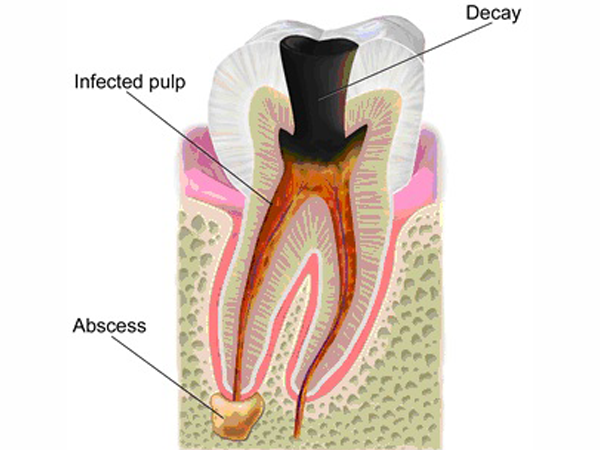

Endodontics is a branch of dentistry concerning dental pulp and the tissues surrounding the root of the tooth.

Root canal treatment is done when the decay is involving the pulp of the tooth .We use specialised instruments to remove the pulp of the tooth and later the canals are filled with a bio compatible material.